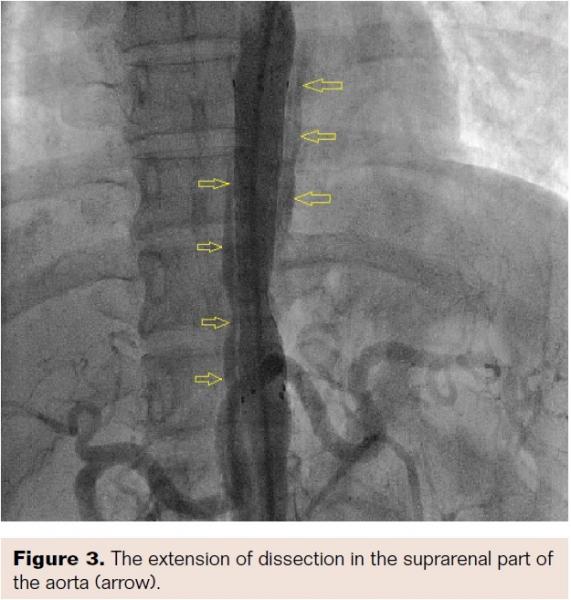

Aortogram confirmed areas of diffuse stenosis and ectasia in the thoracoabdominal aorta, with significant stenosis of the aorta at the level of intervertebral disc between T-11 and T-12 (Figure 2, Video 1). Informed consent for aortoplasty to control secondary hypertension was obtained. Using right femoral arterial access, the occluded segment was crossed using a straight-tip, exchange-length wire (Terumo) and 5 Fr multipurpose diagnostic catheter. The aortic lesion was dilated using an 8 mm x 4 cm Ravel balloon (Bard Peripheral Vascular) at 4 atm; this size was chosen because the narrowest lesion diameter was 5.2 mm (balloon to lesion ratio of 150%). The patient had mild back pain during and after dilation. The pull-back gradient reduced to 50 mm Hg. A dose of 100 mg intravenous tramadol was given. Immediately, a 12 mm x 6 cm E•Luminex self-expanding stent (Bard Peripheral Vascular) was deployed, as we had no covered stent available at the time of intervention. The pull-back gradient reduced further to less than 20 mm Hg. Repeat aortogram by pigtail catheter revealed extensive dissection of the aorta beyond the disease segment (Figures 3 and 4; Videos 2 and 3). No further dilation was attempted. The patient continued to have mild back pain. Beta-blocker was further reinforced by increasing the dose of atenolol to 100 mg twice daily. Her further hospital course was uneventful. At 12-month follow-up exam, the patient continued to be asymptomatic and her hypertension was under control.